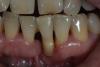

sergio Опубликовано 8 июня, 2013 Поделиться Опубликовано 8 июня, 2013 женщина,50 лет, 31 зуб сама вынимала из лунки и вставляла обратно несколько месяцев. Была сдержанна при разговоре,чтоб случайно не скаканул изо рта Не ходила к гигиенисту ,потому как уверена,что ее зубной камень держит зубы...(наверное она права) Теперь стоит вопрос с тактикой лечения в этой области. Гигиену слава богу уже сделали, зуб 3.1 фиксирован адгезивно к соседним. Фотографий внутриротовых пока нет. Я бы предложил ей убрать все 4 резца и имплантировать 4.2 и 3.2 ,в обл 3.1 - поработать с костью и мягкими тканями,чтоб создать условия для понтика... Пациентка хотела бы ограничиться костной пластикой в обл. 3.1 и постановкой одного импланта.ВАШИ ВАРИАНТЫ? 1.jpg2.jpg3.jpg4.jpg6.jpg8.jpg А 42 почему приговорили? Ссылка на комментарий

art.podzhigant Опубликовано 8 июня, 2013 Автор Поделиться Опубликовано 8 июня, 2013 (изменено) Бир,мягкими тканями имхо можно 3-4 мм нарастить,не больше! А имплантологическая ли вообще эта пациентка,с ее любовью к камням? И зачем вообще здесь все так усложнять? Эта зона эстетически не видна,зачем пациентке удалять еще соседние зубы и делать несколько операций?мне кажется,что лучше в данной ситуации адгезивный мост и все!удалить всегда успеется,а так она еще походит без ухудшения нынешней ситуации... приговорили 42 профилактически.после снятия фундамента в виде камней я ее еще не видел.возможно там теперь все шатается :-) У этой пациентки как раз все очень даже видно. при улыбке и разговоре. Во вторник фото сделаю выложу. Изменено 8 июня, 2013 пользователем art.podzhigant Ссылка на комментарий

art.podzhigant Опубликовано 11 июня, 2013 Автор Поделиться Опубликовано 11 июня, 2013 вот фотки.Пациентка выбрала план лечения с удалением зубов! Ссылка на комментарий